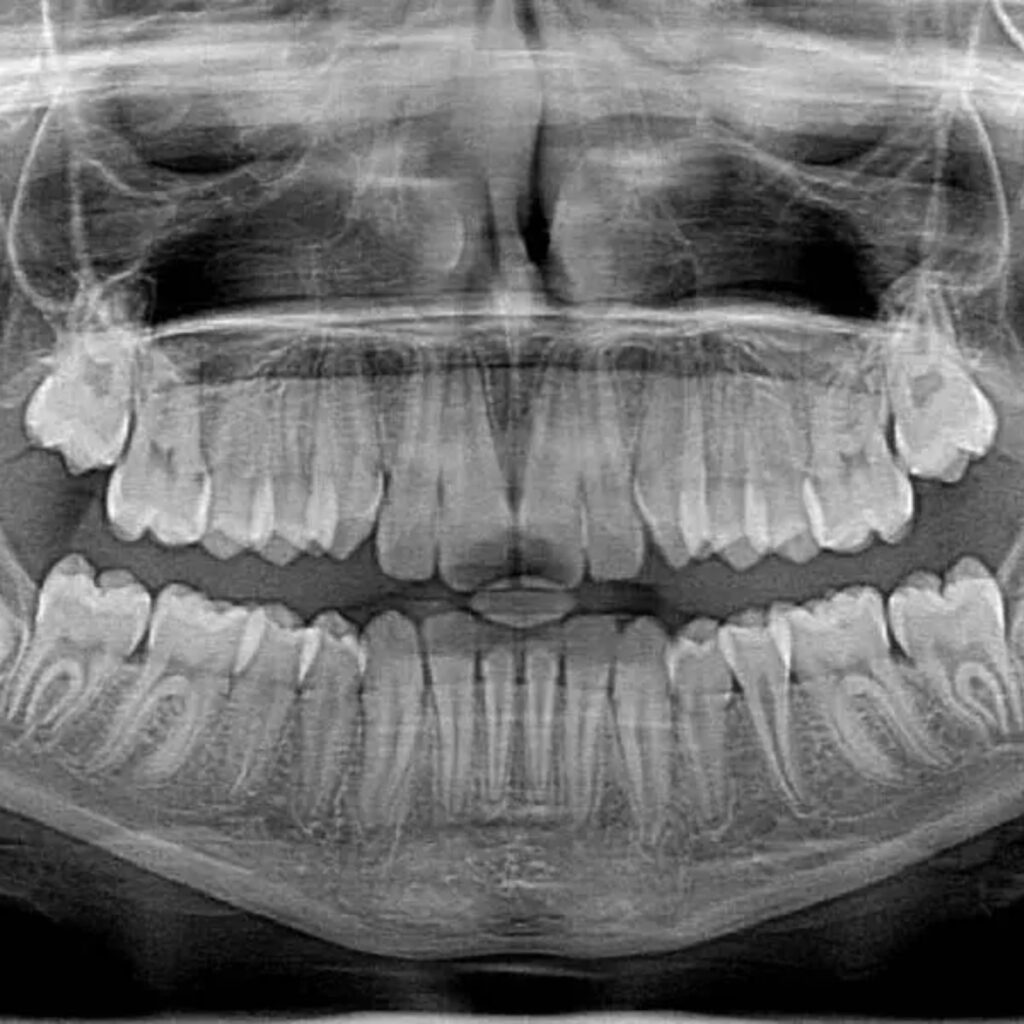

Vijaya Dental Hospital offers advanced dental treatments with modern technology and experienced professionals. It is known for its patient-friendly care, hygiene standards, and high-quality dental services.